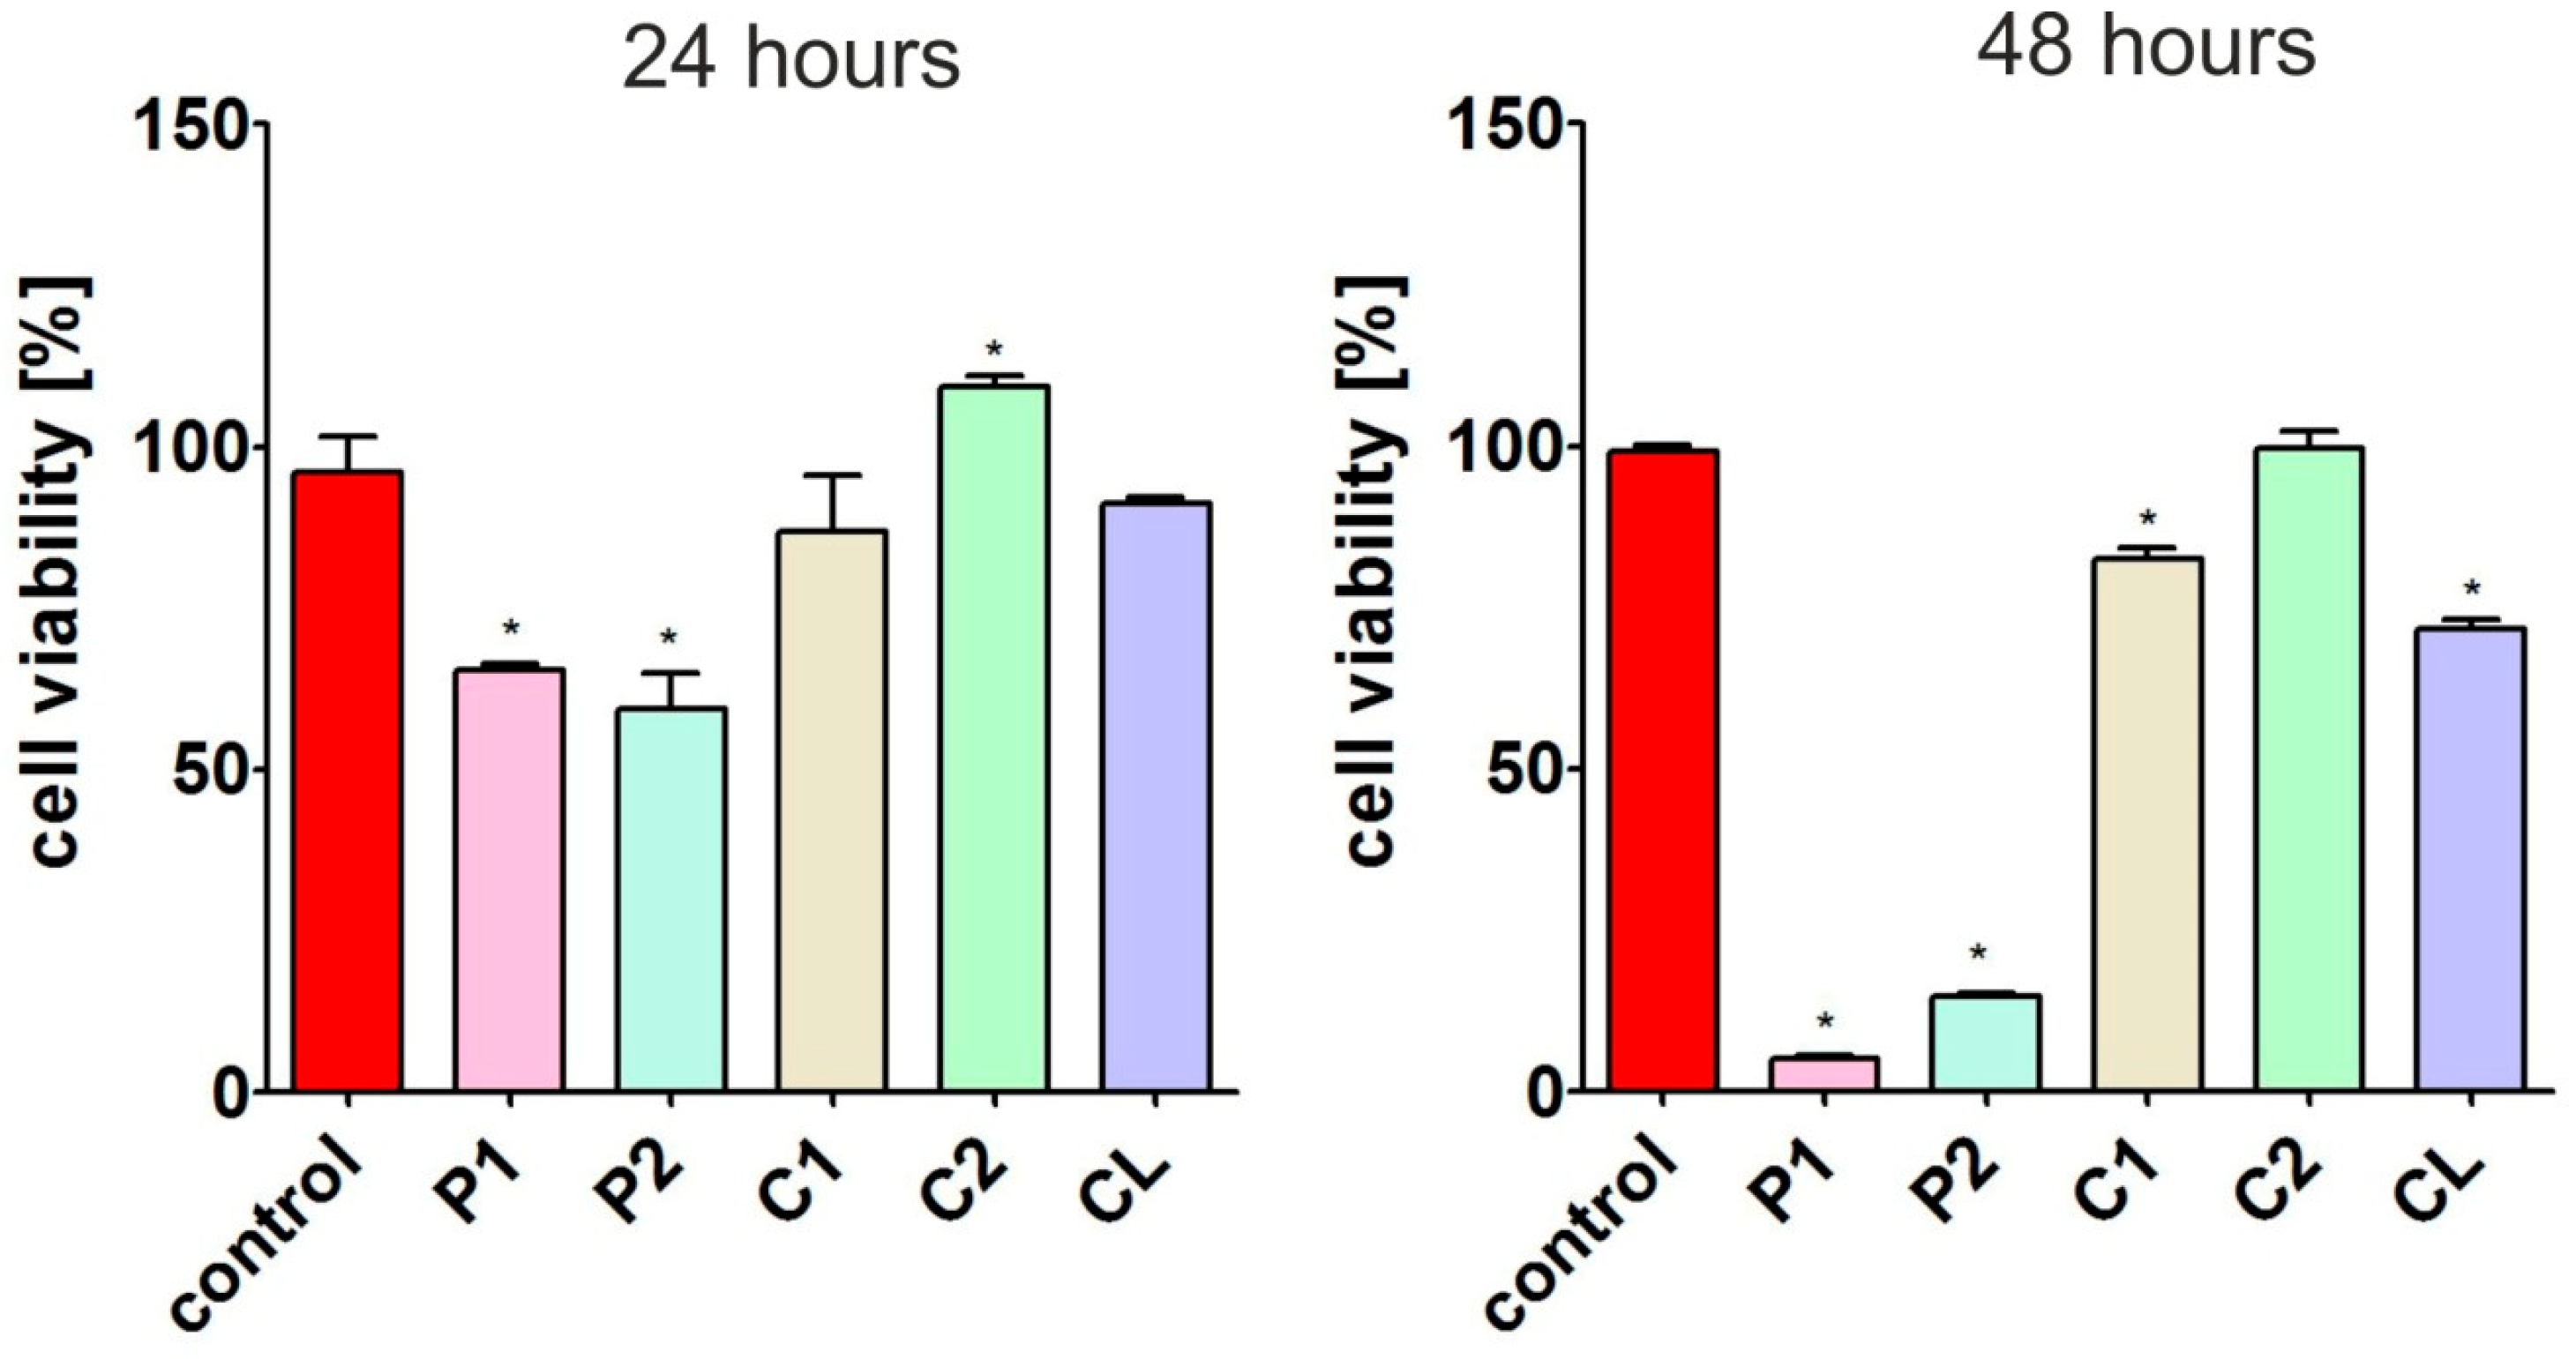

3.7.2. Cytotoxicity